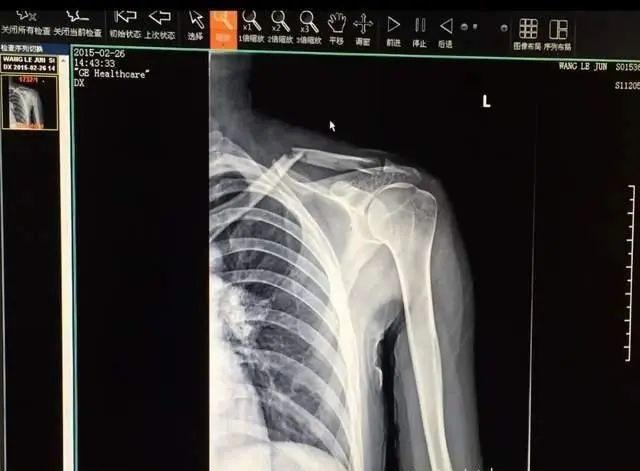

王乐君晒出多张受伤照,称当时锁骨被砸断,做手术打了七颗钢钉。

同时她再次回顾受伤的过程,表示自己受伤是在2015年2月15日,受伤当天自己与胡歌需要拍摄在火车上相遇随后牵手逃跑跳车的戏份。

“这是分开镜头拍的,我们先拍从火车上跳下来的镜头,那时我没有受伤,镜头里的人是正常的。”事故发生在明台拉着程锦云在狭窄火车上高速奔跑的环节,王乐君再次重申,两人在奔跑过程中摔倒,“我先摔倒的,我手里拉着明台,明台离我很近,所以他也摔倒了,明台砸到了我的身上,我当时在现场就动不了了,我是从现场被抬到医院去的,穿着旗袍、戴着头套。”

王乐君也回应了胡歌粉丝提到的“帮忙就医”,“我是自己拜托朋友找的私立医院,第二天早上八点钟做的手术。”而粉丝们找出的胡歌帮忙问诊的截图,王乐君回应是发生在快要杀青时,“杀青前几天钢板翘起来了,骨头和钢板没有长好。”她强调,忍痛把戏拍完后,是自己回到北京联系了积水潭医院的大夫重新做的手术。